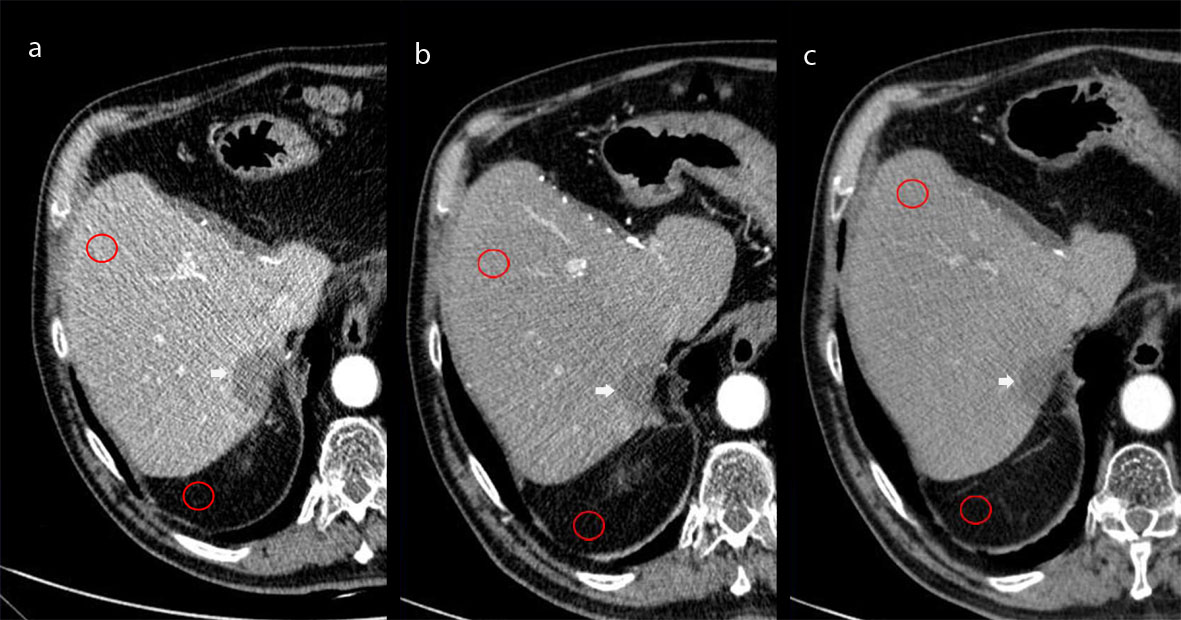

Figure 1 shows the quantitative procedure used in the present study. Hepatic mean attenuation was measured in Hounsfield Units (HU) in three separate areas (left lobe – II segment - and anterior – V - and posterior - VII - segments of the right lobe) on images obtained at the level of the main portal vein on HAP. If one or more liver segments were absent due to previous resection the ROI was positioned in the adjacent inferior or superior liver segment within the same liver lobe. The attenuation values for each liver segment were averaged and one single ROI value resulted from each exam. An attempt was made to maintain a constant ROI area of approximately 2 cm2; the range was 0.8–2.0 cm2. Visible blood vessels, bile ducts, parenchyma areas treated by ablation or TACE, and artifacts were carefully excluded from ROI measurements in the hepatic parenchyma. One ROI was drawn in peritoneal abdominal fat adjacent to the liver, avoiding possible strands, and the standard deviation was recorded for the calculation of the signal-to-noise ratio (SNR) as: Liver Mean HU / SD where SD means standard deviation.

Figure 1. Hepatic mean attenuation measured through one of the three ROIs placed over the fifth segment of the liver and one ROI drawn in peritoneal abdominal fat adjacent to the liver avoiding strands. Images obtained at 80kV (a), 100kV (b), and 120 kV (c).

Figure 1a - c: Hepatic mean attenuation measured through one of the three ROIs placed over the fifth segment of the liver and one ROI drawn in peritoneal abdominal fat adjacent to the liver avoiding strands. Images obtained at 80kV (a), 100kV (b), and 120 kV (c).